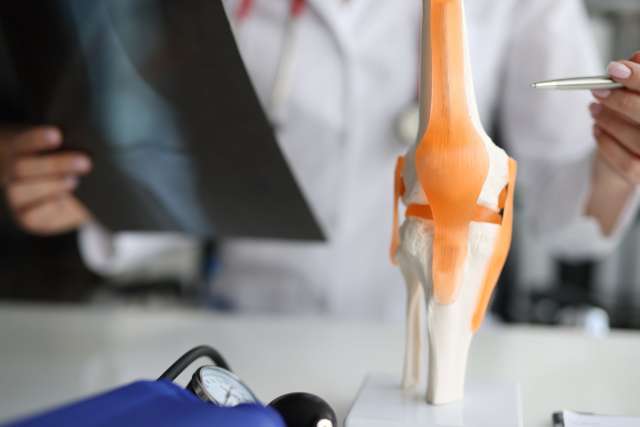

Surgical excellence

We maintain excellent outcomes, even for rare or complex cases. Our minimally invasive techniques result in less pain and faster recovery.

Sports medicine

Sports medicine doctors focus on injuries and conditions related to physical activity. They help you recover and avoid future problems. For severe injuries, orthopedic experts specializing in reconstructive surgery help you get back to doing what you love.